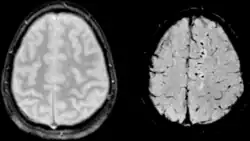

Difúzní axonální poranění je traumatické postižení axonů. Šedá a bílá hmota mají rozdílnou specifickou hmotnost, a proto dochází při úrazu k jejich vzájemnému střižnému pohybu. Axony (bílé hmoty) se natáhnou, poškodí a poté degenerují. Vzniká akceleračním mechanismem poranění. Mezi klinický obraz patří porucha vědomí s ložiskovými příznaky. Dále může být dekortikační rigidita jako odraz postižení axonů motorických drah v úrovni capsula interna a decerebrační rigidita jako důsledek postižení mozkového kmene. Diagnóza se stanovuje za pomoci anamnézy (úraz hlavy, bezvědomí) a negativního CT vyšetření. Mezi pomocná vyšetření patří MRI – drobné ložiskové změny zejm. v oblasti corpus callosum, v subkortikální bílé hmotě, bazálních gangliích, thalamu a Varolově mostu.[1] Léčba zahrnuje hospitalizaci, zajištění vnitřního prostředí, nootropika (piracetam, cca 12 g denně). Prognóza je špatná, není možná úprava ad integrum, bývá perzistence různého stupně fyzického a psychického deficitu.[2]